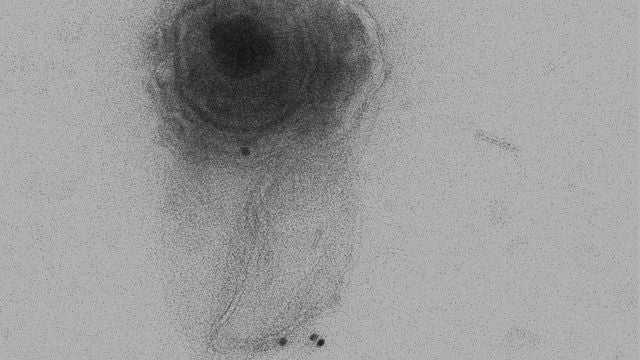

microvesícula conteniendo un virión Sinc

Las microvesículas (MVs) son VEs que se forman a partir de la membrana celular. Los últimos resultados del grupo de López Guerrero, publicados en la revista Journal of Virology, muestran el aislamiento y caracterización de las MVs producidas por células oligodendrocíticas infectadas por HSV-1, y se estudian su relación con la salida viral.

“Por primera vez nuestros resultados han mostrado que HSV-1 puede salir de la célula dentro de MVs. Además, hemos encontrado que estas MVs con viriones en su interior, eran capaces de ser endocitadas por otras células y llevar a cabo de este modo una infección productiva”, señala Bello-Morales.

Según el trabajo, las MVs parecen proceder de la ruta autofágica –mecanismo de regulación de la degradación proteica y de orgánulos celulares–, dado que mostraron marcadores de dicho proceso autofágico, como la proteína LC3B.